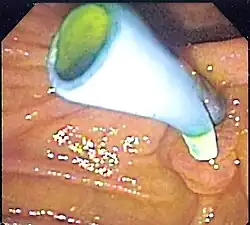

The placement of a colon stent involves endoscopic techniques similar to esophageal stenting. A thin tube called an endoscope is inserted into the rectum and guided through the colon to locate the blockage. Using fluoroscopy or endoscopic guidance, a guidewire is passed through the narrowed area and then removed after positioning it properly. The stent is then delivered over the guidewire and expanded to keep open the obstructed section of the colon. Complications associated with colon stents include perforation of the intestinal wall, migration or dislodgment of the stent, bleeding, infection at insertion site, or tissue overgrowth around it.[10]